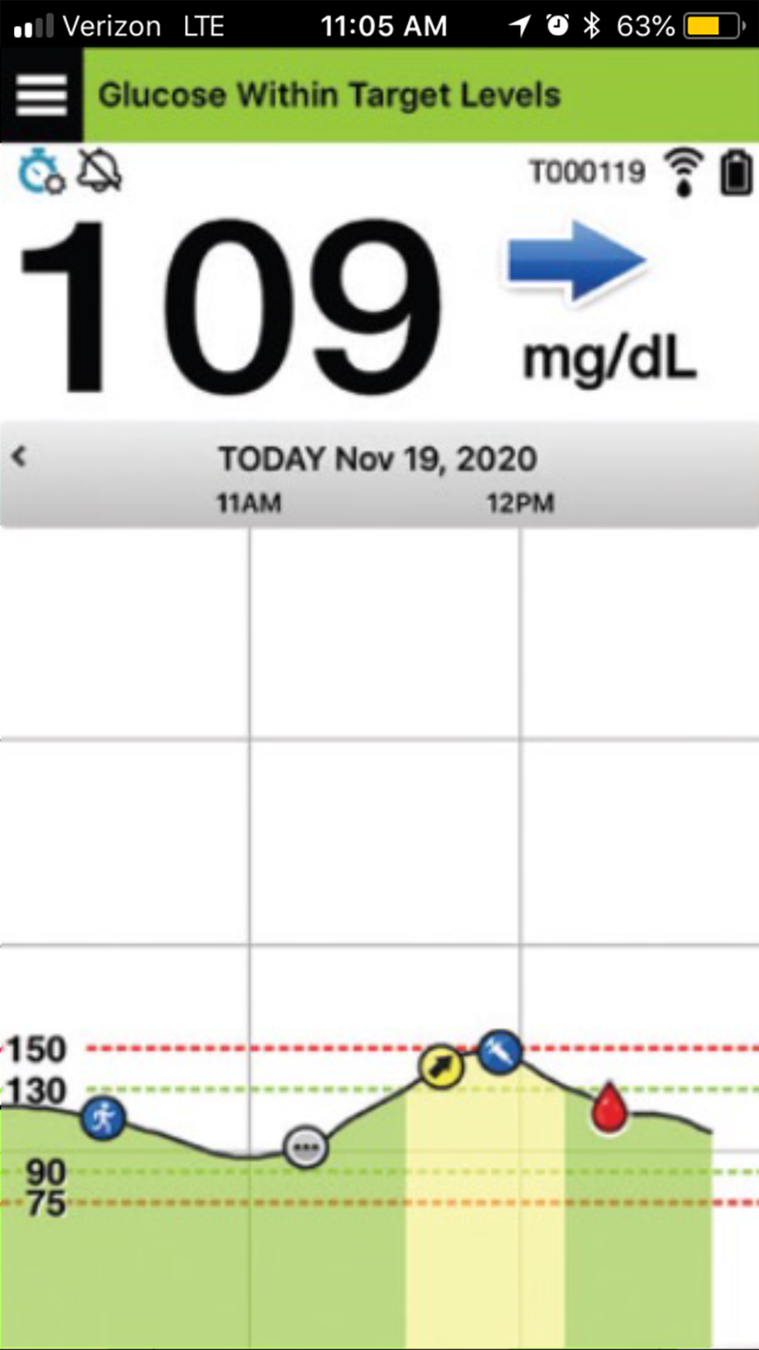

Primero, revisemos la pantalla de inicio

Mi glucosa en la aplicación para móvil Eversense®.

PANTALLA DE INICIO MI GLUCOSA

Cuando abre la aplicación para móvil Eversense®,

se muestran principalmente su nivel

de glucosa actual y una flecha de tendencia.

En la parte superior derecha, puede ver

la intensidad de la conexión entre el transmisor y el sensor, y la carga de la batería que tiene

el transmisor.

PANTALLA DE INICIO MI GLUCOSA

Si ha activado la función No molestar o Perfil temporal, aparecerán los iconos correspondientes

en la parte superior izquierda.

PANTALLA DE INICIO MI GLUCOSA

Y, en la parte inferior, se encuentra el gráfico de tendencia de la glucosa.

Las líneas discontinuas rojas indican los niveles de alerta de glucosa alta y baja, y las líneas discontinuas verdes indican el intervalo objetivo.

Todos los eventos que introduzca en la aplicación (como una calibración, comida, ejercicio

o insulina) o las alertas que reciba, se mostrarán en el gráfico de tendencia con un icono.

PANTALLA DE INICIO MI GLUCOSA

Si ha activado la función No molestar o Perfil temporal, aparecerán los iconos correspondientes en la parte superior izquierda.

Puede consultar la sección Utilizar la aplicación para móvil en la Guía de consulta rápida del sistema de MCG Eversense® E3 en cualquier momento.